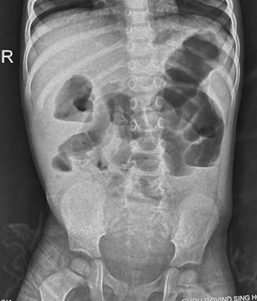

However, in small bowel obstruction, there is too much gas in the small bowel loops compared to the colon. Conversely, in colon obstruction with intact ileocecal valve, there is too much gas in the colon (Figure 3) compared to the small intestine and there is little or no gas in the rectum.5 The lack of gas in the rectum, however, is a late sign of bowel obstruction, so patients who present early in their disease process may have gas in the rectum on radiograph.

Figure 3 Anteroposterior supine abdominal radiograph in a 4-year-old child showing dilatation of bowel with smooth walls with too much gas in colon (haustra can be seen to identify colon) and absence of gas in the rectum suggestive of distal large bowel obstruction at level of rectosigmoid junction probably due to Hirschsprung’s disease.